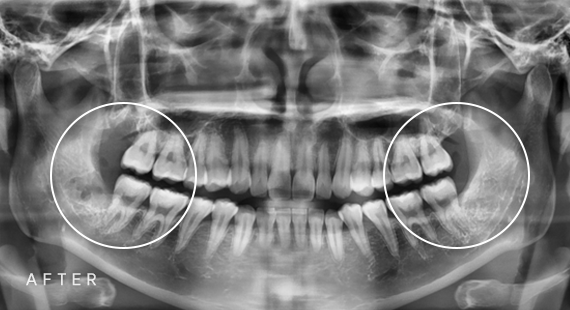

임플란트